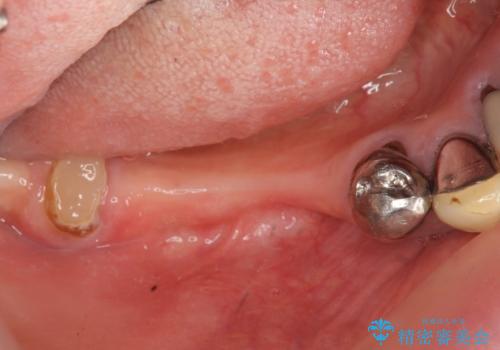

- 歯を失い噛めないこと、骨の幅が狭く他院でインプラント治療が難しいと断られ、当院でのインプラント治療が可能かどうか相談来院されました。

骨の造成、角化歯肉の移植を行いインプラント周囲の環境を整えた治療を計画します。

遊離歯肉移植術(硬い歯ぐきのインプラント周囲への移植)を行ったことで、炎症に強く歯ブラシのしやすい環境をインプラント周囲に整えることができました。